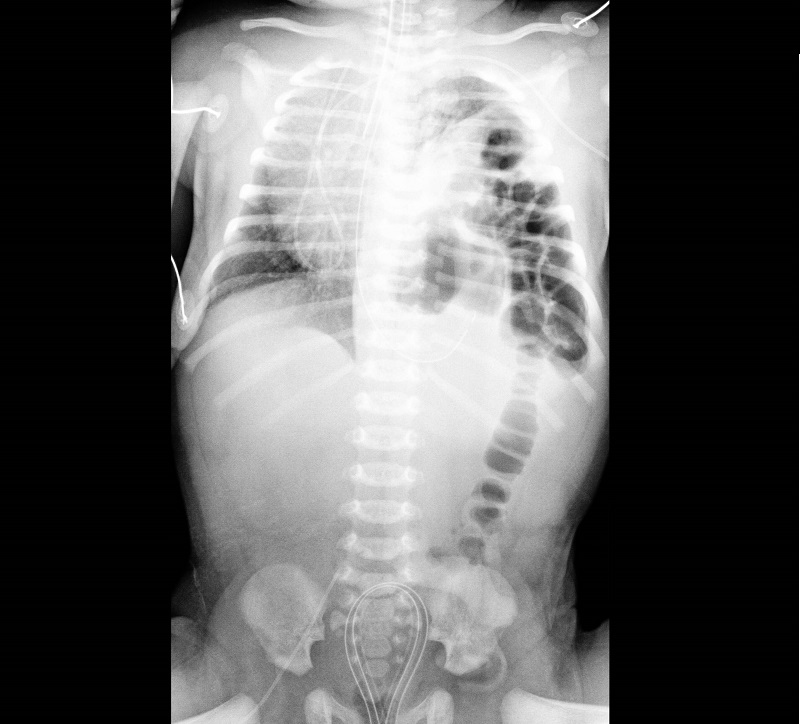

Sta bene e ha cominciato ad alimentarsi il neonato operato la settimana scorsa al Garibaldi-Nesima…